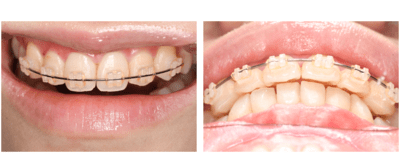

症例⑥

前歯の歯並びがきになる

| 年齢 | 20代女性 |

|---|---|

| 主訴 | 前歯の歯並びがきになる |

| 治療内容 | プチ矯正(上顎のみ) |

| 治療期間 | 2ヶ月 |

| 費用 | 165,000円(税込) (2022年2月現在) |

| リスク・副作用 | プチ矯正は全ての方に適応になるわけではありません。矯正中は器具が唇に接触するため口内炎ができやすくなります。歯が動かないなどで期間が長くなることもあります。 スペースをつくるために歯を削ることがあります。 |

| 治療方針 | 以前マウスピース矯正をしていたが、後戻りで前歯がやや前方にでてきてしまっています。 上顎下顎ともにあともどりがあり、歯と歯の間に若干スペースができている。 患者の希望が上顎だけだったので、下顎はそのままで、上顎のみ矯正をすることとした。 矯正は基本的にはスペースを作るため歯を削ることが多いが、今回のケースではスペースを閉じるだけなので、歯を削らずに行う計画を立てた。 |

ブラケット・ワイヤー装着

まずはブラケットを装着。審美的になるべく阻害がないように、透明なブラケットを使用した。

2週間後

ワイヤーはまだたわみがあるが正中はやや閉鎖してきた。

更に2週間後

正中はほぼ閉じた。ワイヤーのたわみも無くなってきた。

もうすこし左上2が頬側に出てほしい。

完成。

保定もかねてワイヤー(1622SS)変更。

1ヶ月後

ブラケット除去。

同時に予定していた保定装置のマウスピース用の印象をおこなった。

正中離開、左上2の位置、被蓋関係、全ての改善をすることができた。しかもたったの2ヶ月!

翌日、ハードタイプ1ミリのマウスピースを保定装置として使用させるために作成しお渡した。

ビフォーアフター写真

治療前

治療後